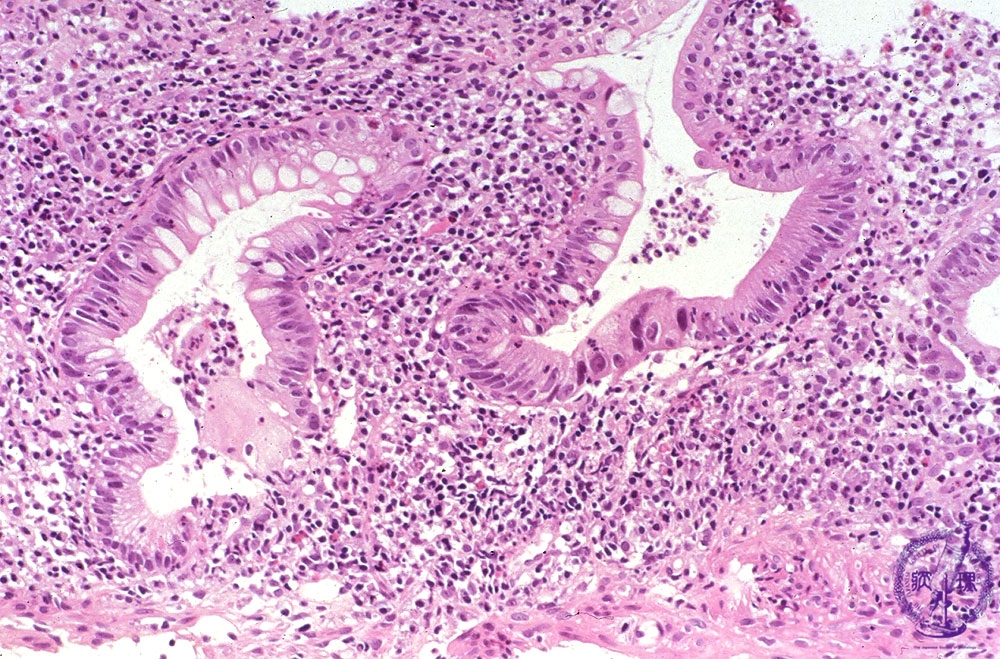

Microscopic view (H&E stain, high power): Acute ulcerative colitis with severe inflammation including crypt abscess formation.

Click the image to see the enlarged image.